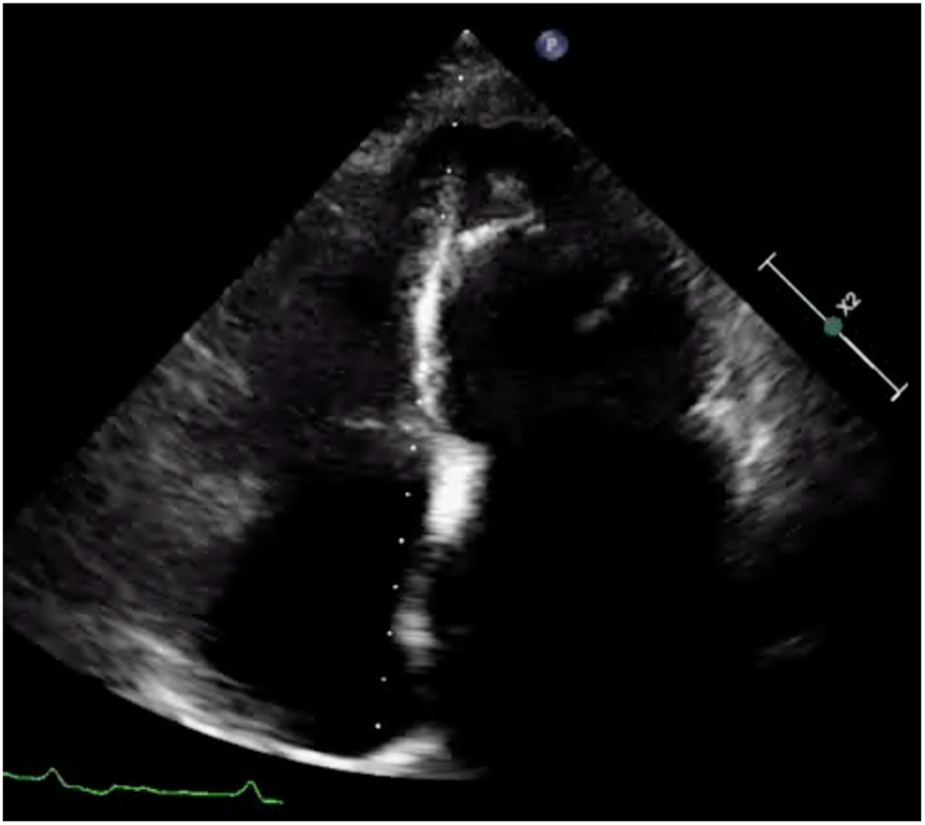

Electrocardiography showed atrial fibrillation with a left bundle branch block (LBBB) and Q waves in leads I and aVL (Figure 1). Transthoracic echocardiography demonstrated left ventricular and biatrial enlargement, with measured dimensions of a left ventricular end-diastolic diameter (LVDEd) 63 mm, left atrial systolic diameter (LAS) 58 mm, and right atrial diameter (RA) 43 mm. Additional findings included apical hypertrophy, increased endocardial echogenicity, diffusely hypokinetic wall motion, and a left ventricular ejection fraction (LVEF) of 40% (Figure 2). No left ventricular outflow tract or mid-cavity blood flow acceleration was detected.

Figure 2

Apical 4-chamber view of the left ventricle showing apical hypertrophy in addition to asynergy in the apical walls with high echogenicity.